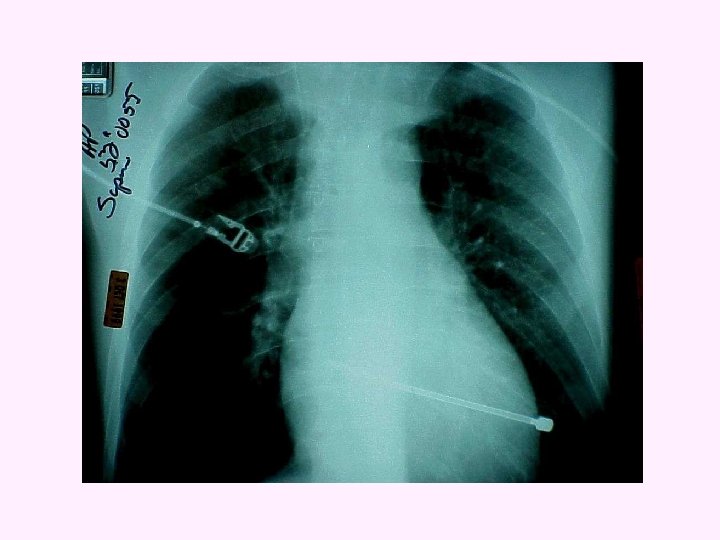

TANSİYON PNÖMOTORAKS * İnspiryumda havanın plevral alana girmesi, ancak ekspiryumda çıkamaması ve gittikçe artması sonucu yaralanmış akciğere ve sağlam akciğer ile kalbe ve büyük damarlara baskı yapması sonucu gelişen bir durumdur.

TANSİYON PNÖMOTORAKS

Tansiyon pnömotoraks varsa göğüs ön duvarına iğne ile girilir yada göğüs tüpü yerleştirilir Damar yolu açılır ve sıvı perfüzyonuna başlanır Gerekli ise, perikardiyosentez yapılır Kosta kırıkları multipl travma olarak kabul edilir ve başka yaralanmalar araştırılır